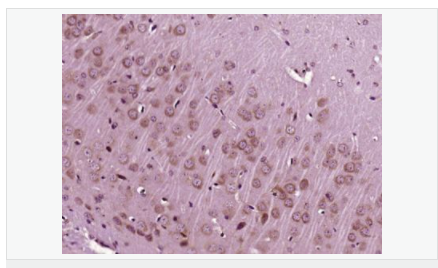

| 英文名稱 | IGF 1 |

| 中文名稱 | 胰島素樣生長因子1抗體 |

| 別 名 | IBP1; IGF 1; IGF I; IGF-1;IGF IA; IGF IB; IGF1; IGFI; IGFIA; Insulin like growth factor 1 (somatomedin C); Full=Insulin-like growth factor I; Insulin Like Growth Factor 1; Insulin like growth factor IA; Insulin like growth factor IB; Mechano growth factor; MGF; Mechano growth factor; MGF; Somatomedia C; Somatomedin C; IGF1_HUMAN. |

| 研究領域 | 免疫學 發(fā)育生物學 信號轉導 生長因子和激素 糖尿病 |

| 產品應用 | WB=1:500-2000 ELISA=1:5000-10000 IP=1:20-100 IHC-P=1:100-500 IHC-F=1:100-500 IF=1:100-500 (石蠟切片需做抗原修復) not yet tested in other applications. optimal dilutions/concentrations should be determined by the end user. |

| 分 子 量 | 7.7/21kDa |

| 產品介紹 | The protein encoded by this gene is similar to insulin in function and structure and is a member of a family of proteins involved in mediating growth and development. The encoded protein is processed from a precursor, bound by a specific receptor, and secreted. Defects in this gene are a cause of insulin-like growth factor I deficiency. Several transcript variants encoding different isoforms have been found for this gene.[provided by RefSeq, Mar 2009] Function: The insulin-like growth factors, isolated from plasma, are structurally and functionally related to insulin but have a much higher growth-promoting activity. May be a physiological regulator of [1-14C]-2-deoxy-D-glucose (2DG) transport and glycogen synthesis in osteoblasts. Stimulates glucose transport in rat bone-derived osteoblastic (PyMS) cells and is effective at much lower concentrations than insulin, not only regarding glycogen and DNA synthesis but also with regard to enhancing glucose uptake. Subcellular Location: Secreted. DISEASE: Defects in IGF1 are the cause of insulin-like growth factor I deficiency (IGF1 deficiency) [MIM:608747]. IGF1 deficiency is an autosomal recessive disorder characterized by growth retardation, sensorineural deafness and mental retardation. Similarity: Belongs to the insulin family. SWISS: P05019 Gene ID: 3479 Database links: Entrez Gene: 3479 Human Omim: 147440 Human SwissProt: P05019 Human Unigene: 160562 Human Important Note: This product as supplied is intended for research use only, not for use in human, therapeutic or diagnostic applications. 胰島素樣生長因子1(IGF-1)是一種生長調節(jié)激素,由肝分泌并入血液循環(huán)的中性多肽,具有調節(jié)生長和代謝、胰島素樣及促細胞分裂的活性,主要作用于成人。 |